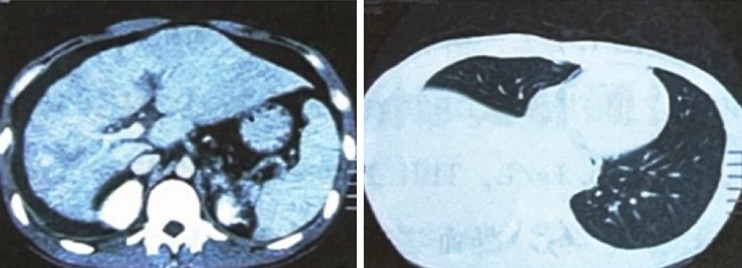

辅助检查:血常规:WBC 5.86x109/L,粒细胞比率82%,RBC 4.98x1012/L,HGB 148g/L,PLT 121x109/L。腹水常规:蛋白11g/L,粘蛋白试验(+),细胞数70x106/L,分叶核占25%。胸水常规:蛋白15g/L,粘蛋白试验(-),细胞数90x106/L,分叶核占40%。肝功:ALT 31U/L,ALP 113U/L,GGT 131U/L,TP 46.6g/L,ALB 26.1g/L,TBIL 27.4μmo/L,DBIL 11.2μmol/L。肝炎病毒标志物(-)。凝血三项:PT 15秒,Fg 3.68g/L,PT活动度76%。CA12-5 313.2U/ml。肾功、血沉、结核抗体及免疫自身抗体均未见异常。彩色超声:右肝静脉管腔未显示,左肝静脉增宽,入口狭窄,中肝静脉入口未显示,中肝静脉与左肝静脉之间交通支形成,下腔静脉肝后段管腔变窄(图1)。

图1  肝静脉和下腔静脉彩色超声所见